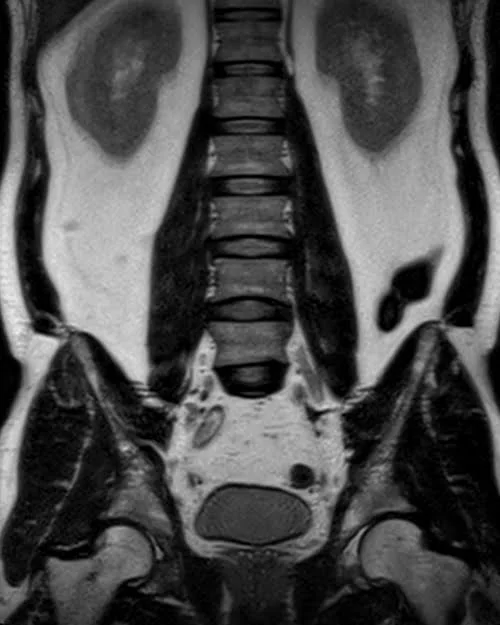

l plexus mri SPACE 3D coronal images